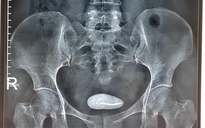

Dị vật được cho là vòng tránh thai đặt cách đây 22 năm đã "đi lạc" vào bàng quang của bệnh nhân V.T.Đ

ẢNH: BVCC

Qua thăm khám, siêu âm và chụp X-quang cho thấy một vòng tránh thai nằm trong bàng quang, bề mặt có nhiều sỏi bám. Đây được xác định là nguyên nhân trực tiếp gây kích thích và xuất huyết đường tiểu, khiến các triệu chứng tái diễn kéo dài.